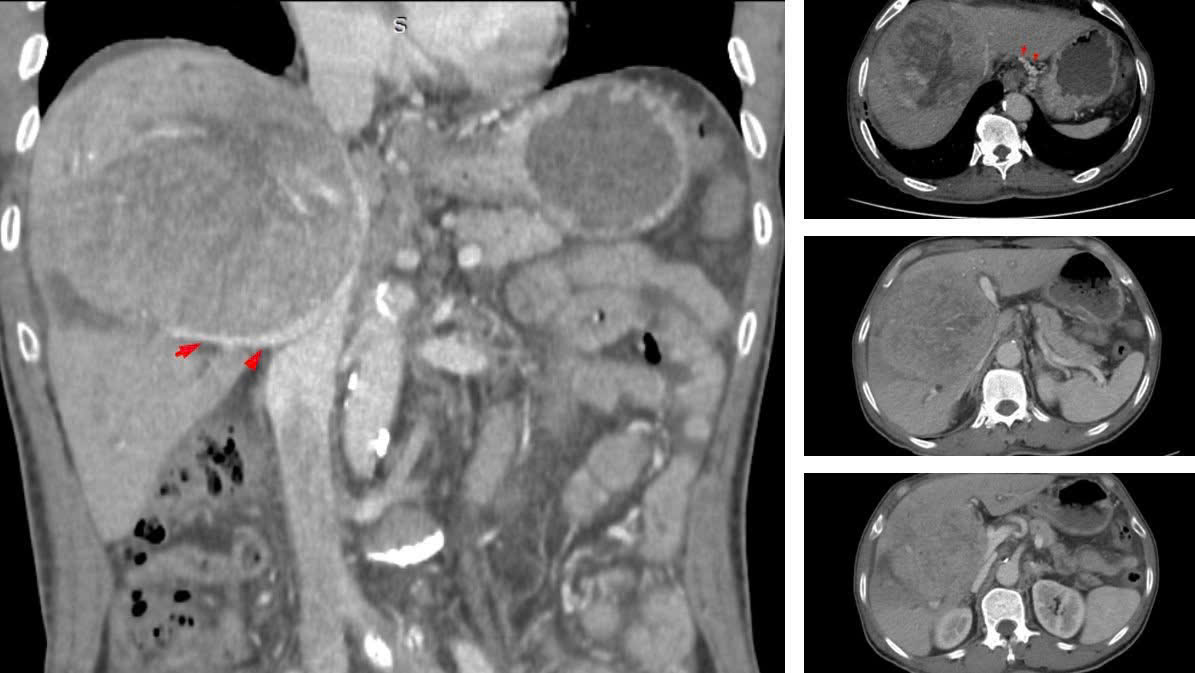

Tháng 7/2023, lần mổ đầu tiên Khối u trung tâm hơn 10cm, đè đẩy làm mất các mốc giải phẫu

Theo BSCKII Nguyễn Trường Giang, Phó Giám đốc Trung tâm Phẫu thuật Gan mật – Tiêu hóa, ngay khi tiếp nhận, đây đã là một ca bệnh rất nặng. Khối u khổng lồ chiếm gần hết nhu mô gan, chèn ép rốn gan và tĩnh mạch, gây ra tình trạng cổ chướng nhẹ và phù hai chân.

Các bác sĩ đã quyết định tiến hành cuộc đại phẫu cắt gan trung tâm kéo dài gần 8 giờ. Tuy nhiên, sau mổ, bệnh nhân xuất hiện biến chứng rò mật và hẹp tắc đường mật phân thùy sau. Ê – kíp đã nỗ lực đặt dẫn lưu đường mật qua da nhưng không thể can thiệp đặt stent xuống ống mật chủ. Đồng thời, tình trạng nhiễm trùng đường mật diễn biến nặng với vi khuẩn đa kháng thuốc kèm theo suy gan, khiến quá trình điều trị kéo dài với diễn biến vô cùng phức tạp.